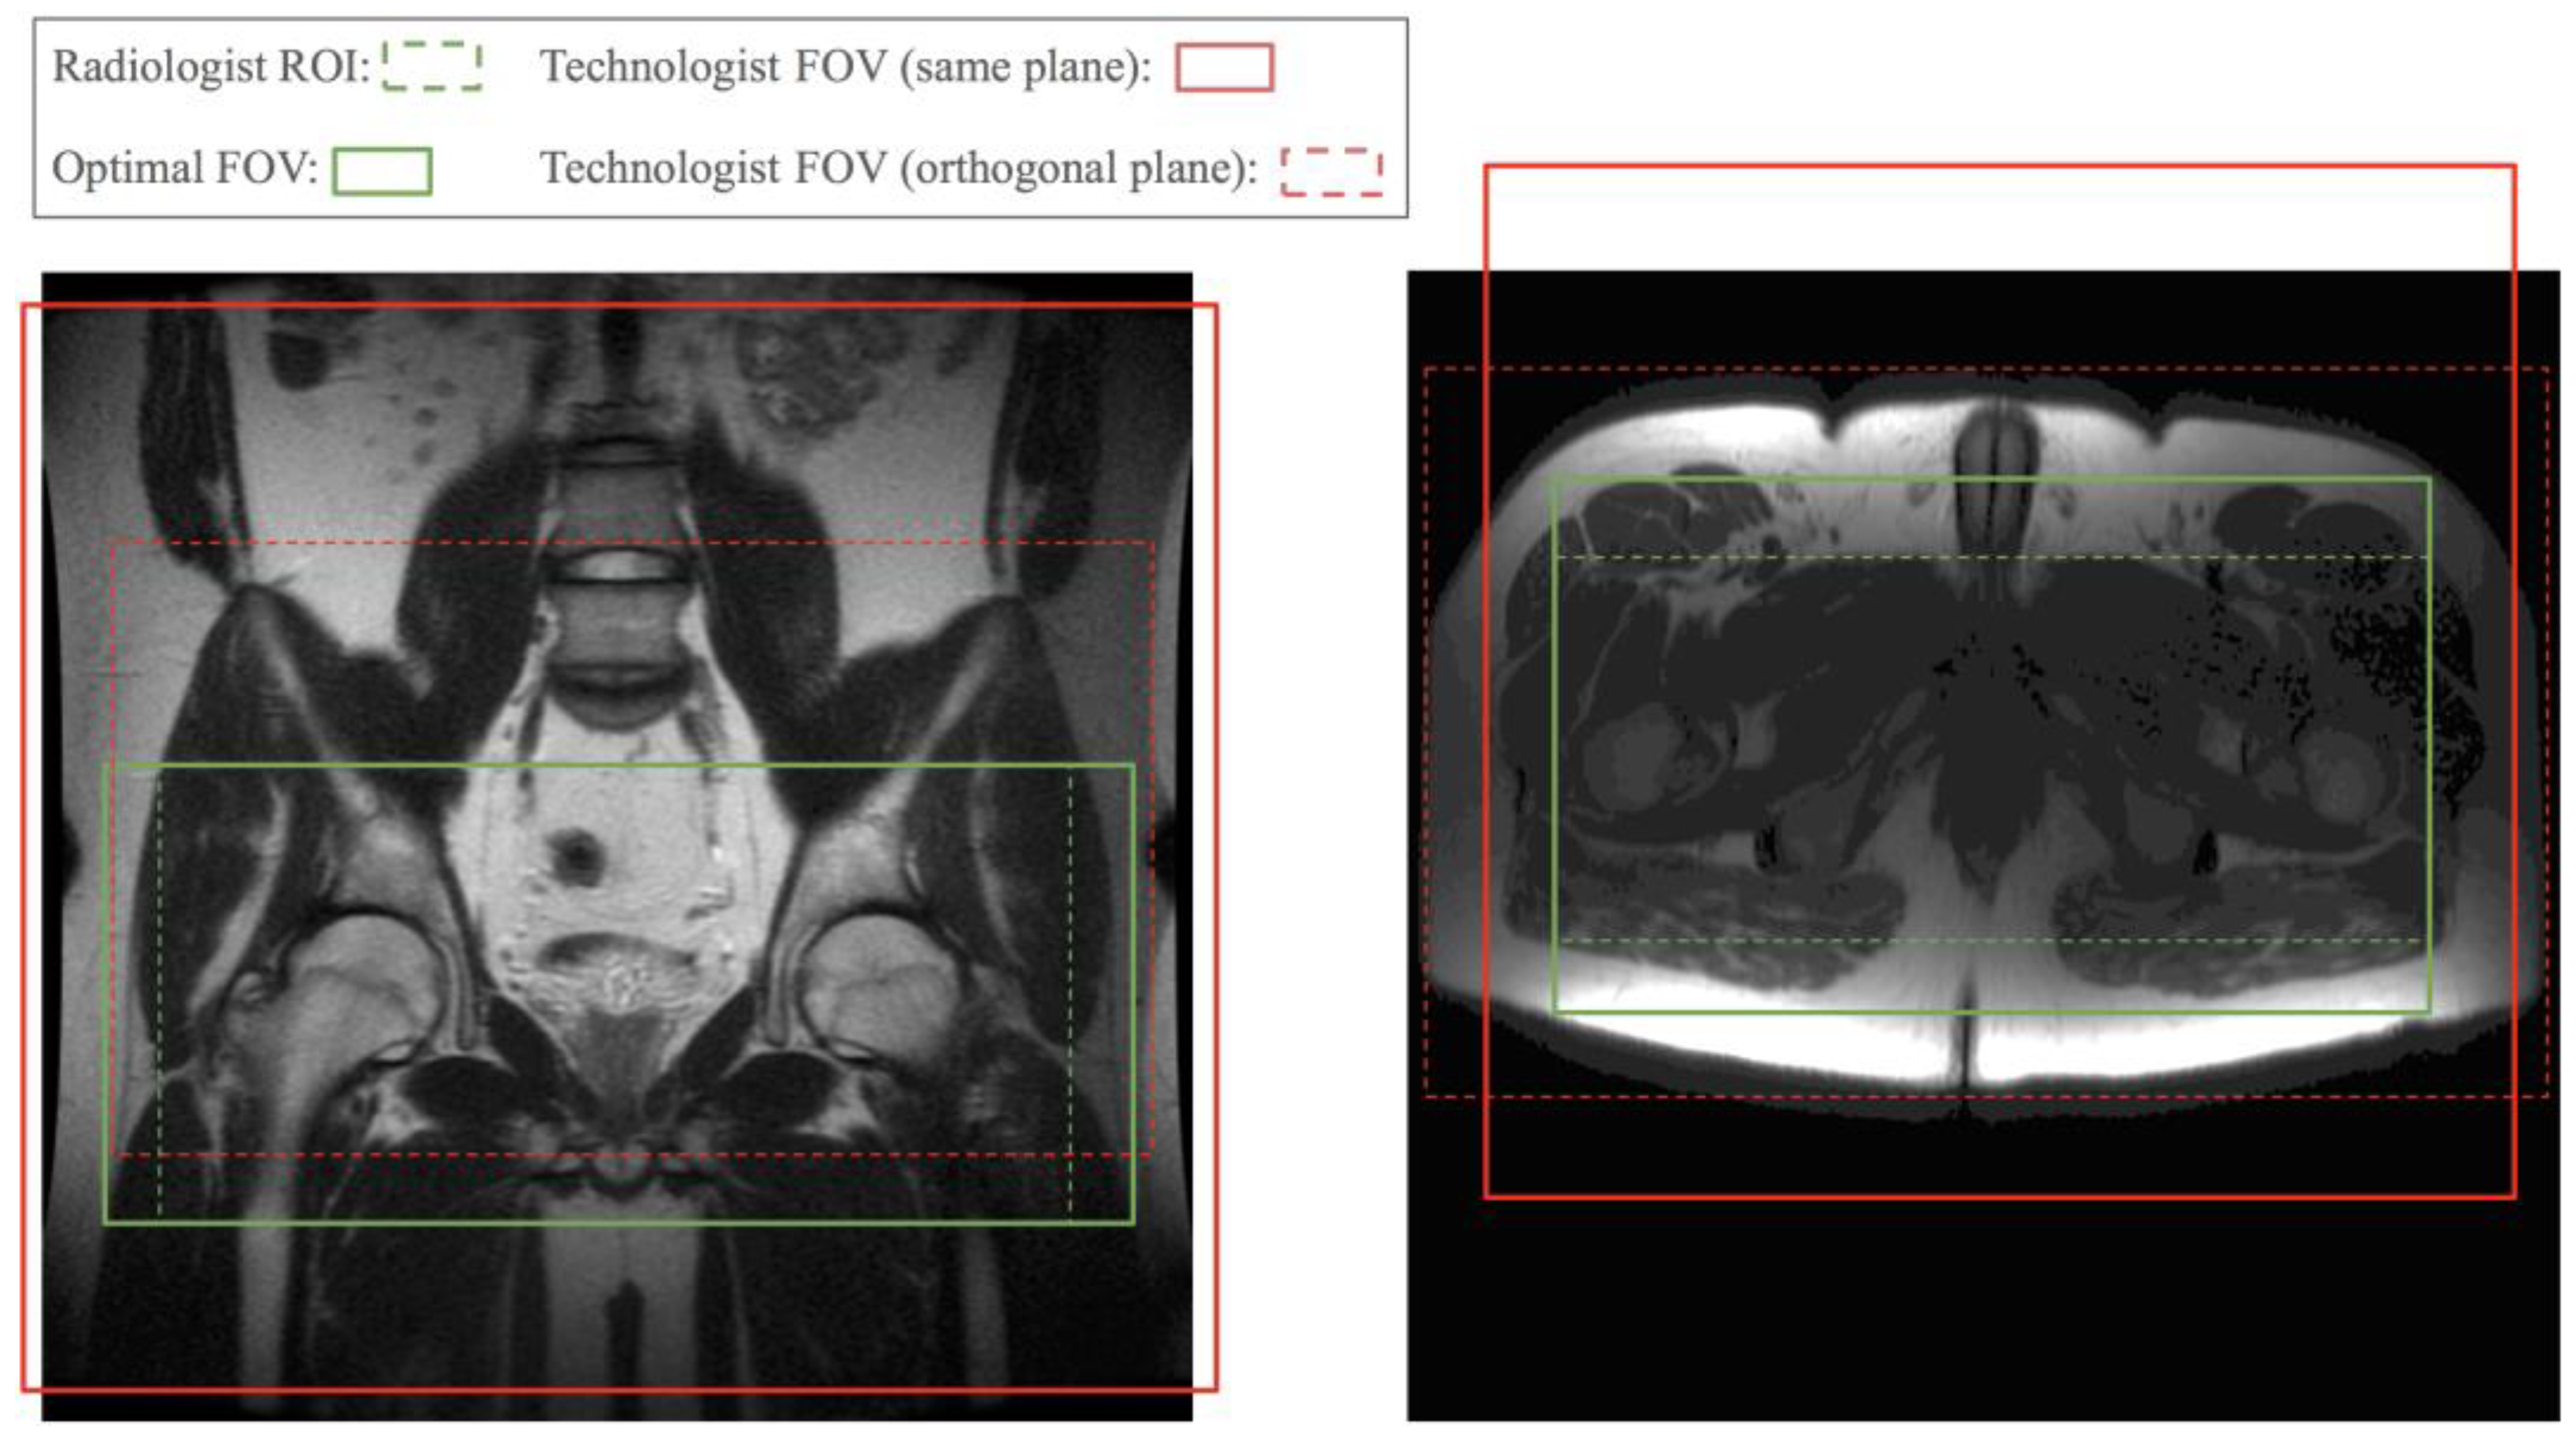

At the beginning of clinical MRI exams, a set of localizer images with low spatial resolution and a large field of view (FOV) is collected to help define more precise imaging regions for the following diagnostic image acquisitions. MRI technologists select a FOV on the localizer images to plan the next scan. This manual step slows down the scanning workflow, prolonging the overall exam time, and influences image quality. Technologists are often not fully informed of the radiologist’s requirements for the region of interest (ROI). Figure 1 shows two examples of FOVs prescribed by a technologist compared to a radiologist’s required FOV. Poor FOV assignments may lead to images with relevant anatomy truncated and a non-diagnostic exam. A conservatively assigned large FOV costs scan time or resolution. Therefore, we propose automating the FOV assignment with models trained by radiologists’ ROI labels to obtain near optimal FOVs and streamline scans after the initial localizer.

Figure 1. Technologist-prescribed FOV, and slice range for the orthogonal plane, compared with optimal FOV derived from radiologist’s ROI. Red solid boxes represent the FOV prescribed for the same plane as the localizer image. Red dashed boxes indicate the slice range and left–right FOV prescribed for the plane orthogonal to that of the localizer image, i.e., axial plane for the coronal localizer and vice versa. The red dashed box in the left sample truncated the bottom part of the ROI. The other three red boxes are much larger than needed.